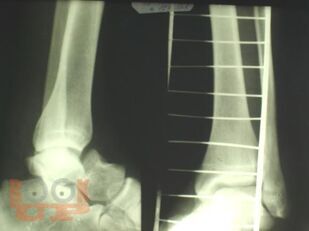

Чрескостный остеосинтез аппаратами внешней фиксации при лечении повреждений таранной кости

Учебно-методическое пособие содержит необходимую информацию для врачей по вопросам механизма повреждения, клиники, диагностики, осложнений и лечения переломов таранной кости. В пособии представлены биомеханические особенности дистального отдела нижней конечности. Основное внимание уделено проблеме лечения переломов таранной кости, а также осложнений переломов и переломо-вывихов таранной кости в виде развития аваскулярного некроза таранной кости. Приведены компоновки аппаратов внешней фиксации при различных типах повреждений.

В пособии обобщен более, чем 30-летний опыт лечения пациентов с переломами и переломо-вывихами таранной кости.